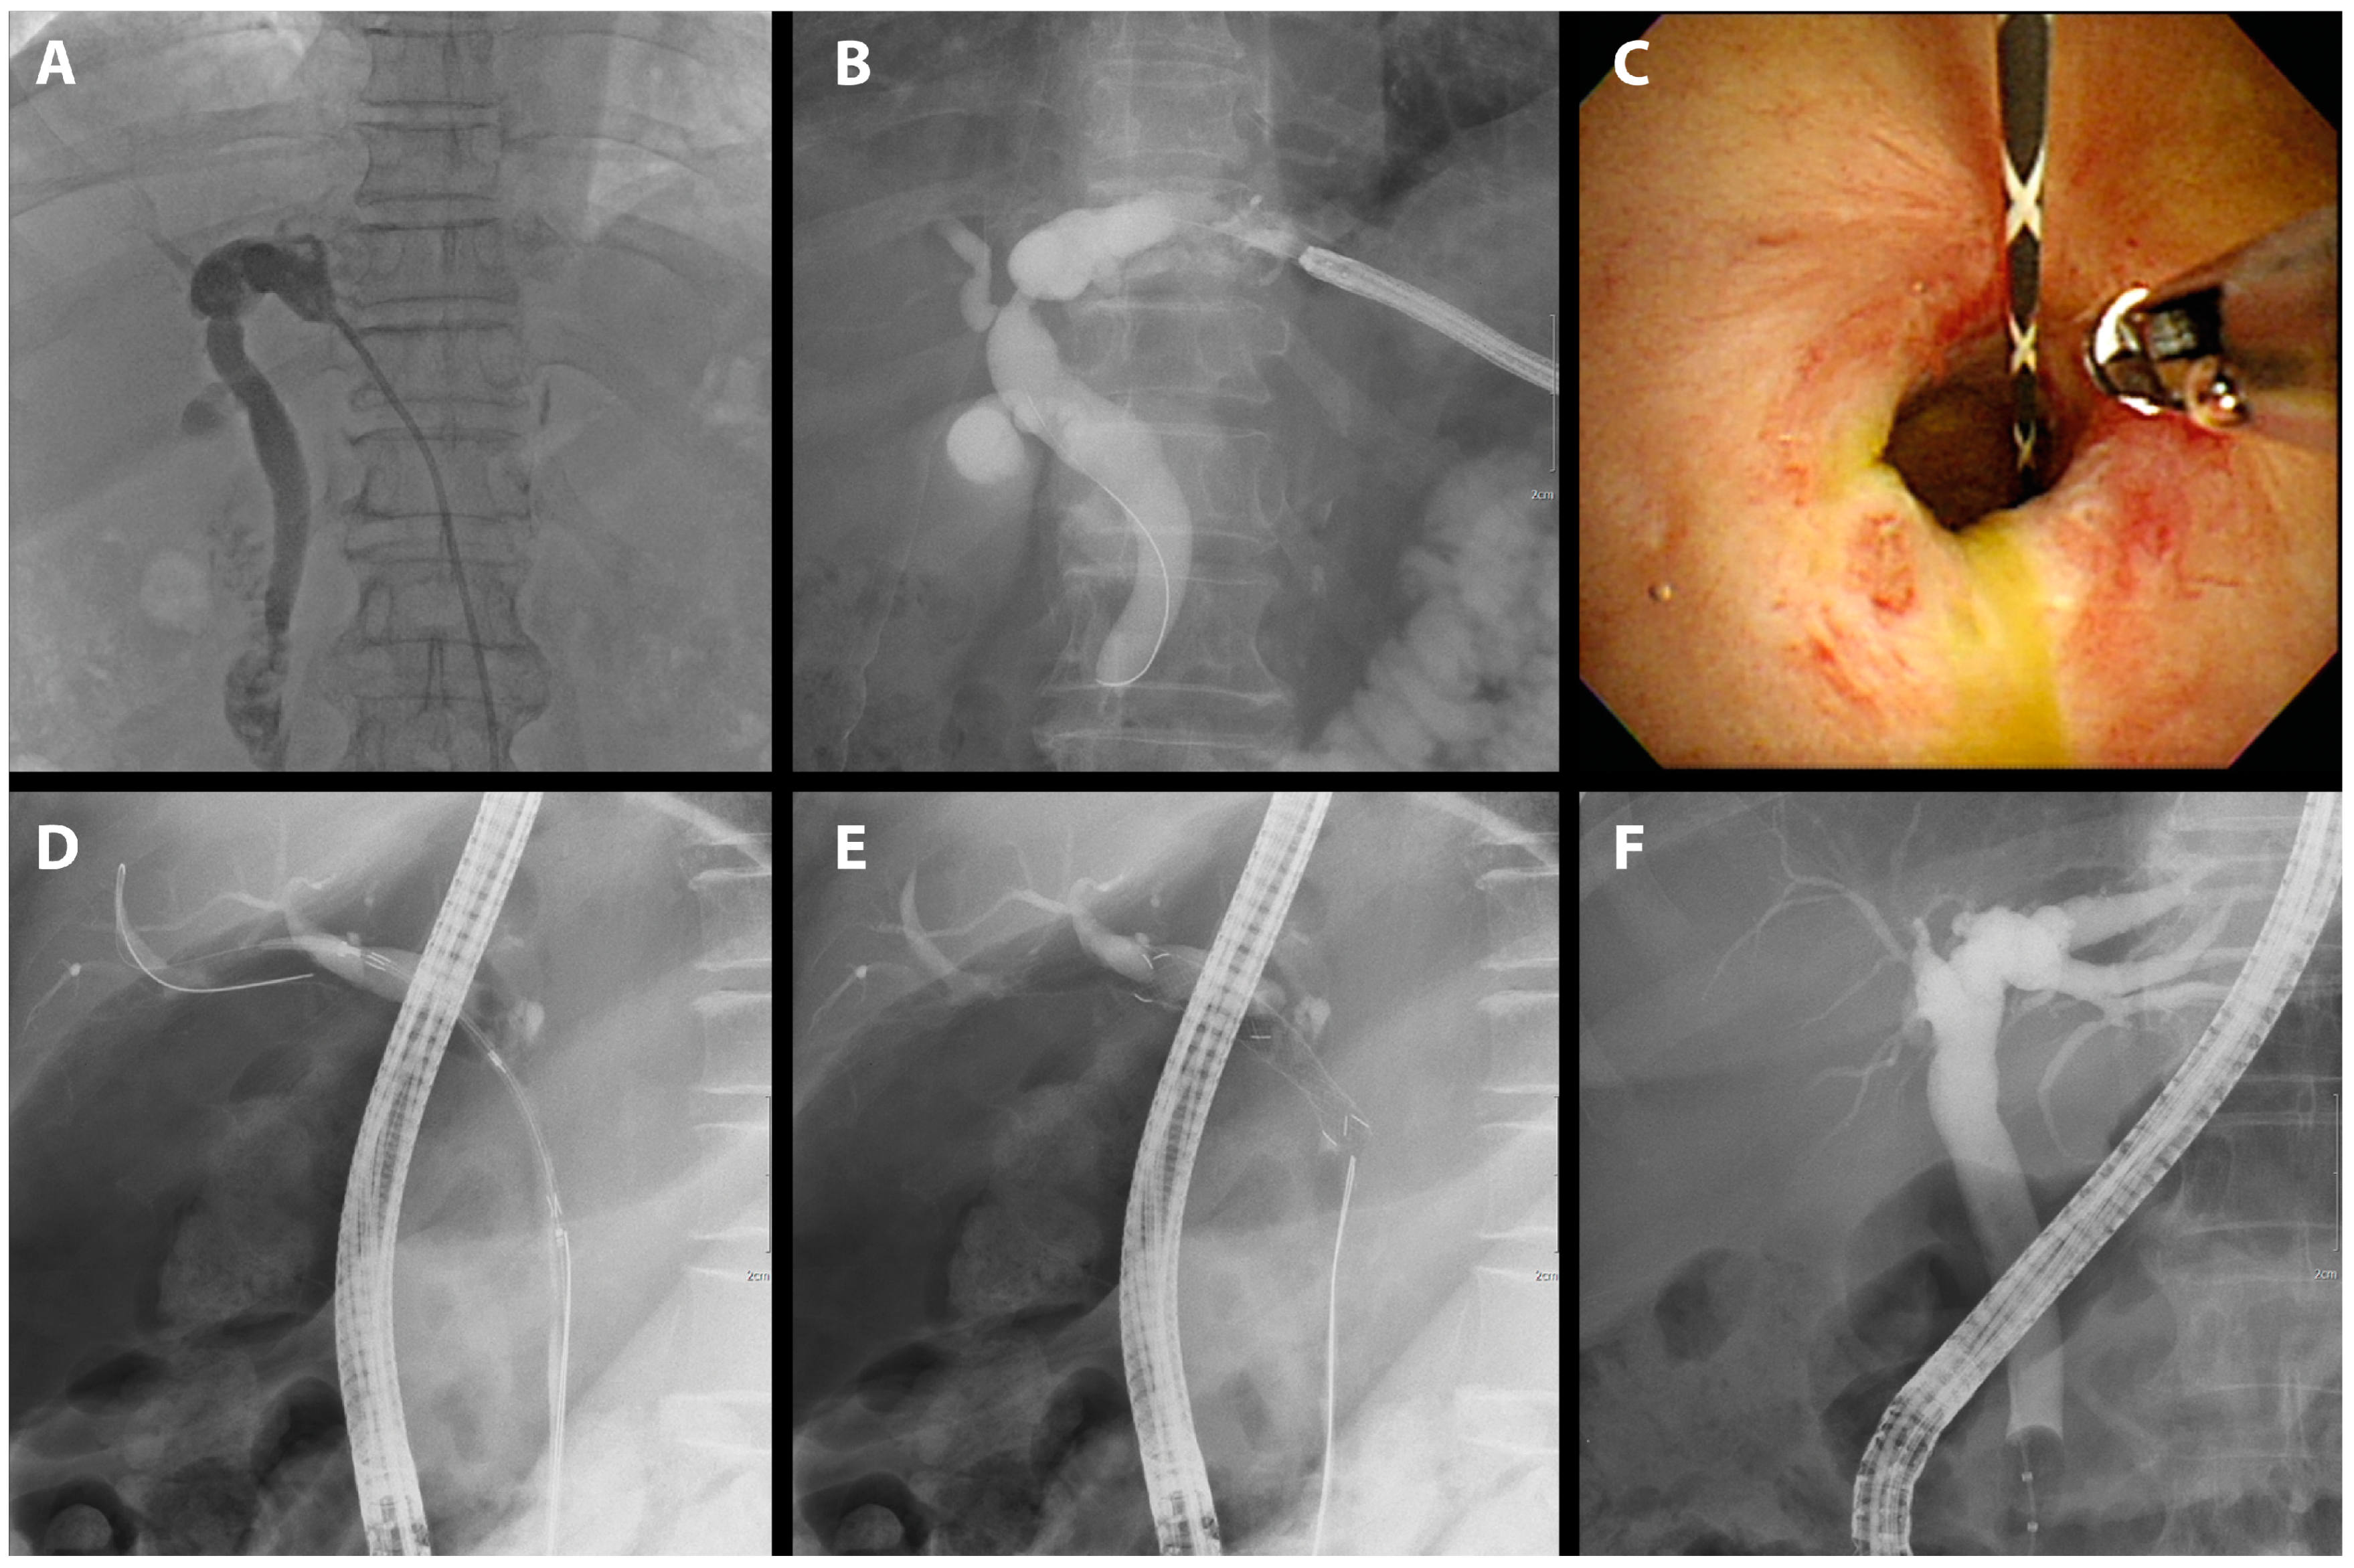

Despite the potential of non-surgical BBS emanating from diverse etiologies including primary sclerosing cholangitis and IgG4-related cholangiopathy, their representation in our study was scant. Hence, we consolidated non-surgical BBS cases into a singular category. For the patient presented in this study, only benign fibrotic tissue was confirmed histologically, and there were no IgG4 or other pathological findings, so the patient is being followed up on an outpatient basis after treatment of the stricture (Figure 5).

Figure 5.

FCSEMS treatment of BBS. A case of BBS diagnosed by histological findings and treated with FCSEMSs is presented. (A) Cholangiography with PTBD confirmed left biliary stricture. (B) Percutaneous transhepatic cholangioscopy was used for histological examination. (C) Histological examination was performed on the area of biliary stricture. (D) An FCSEMS (10 mm in diameter, 4 cm in length; KAFFES) was inserted into the BBS. (E) The FCSEMS was successfully deployed. (F) After 12 months of FCSEMS use, including three replacements, the stent was removed, and the procedure was terminated after confirming that the BBS had resolved.